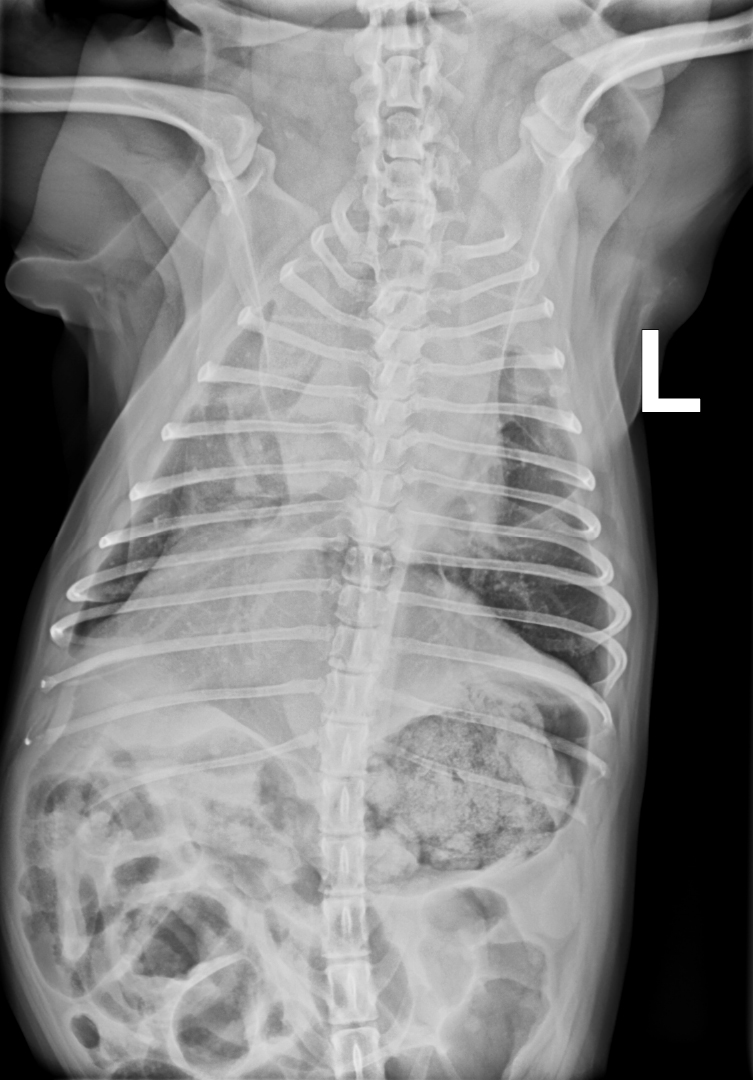

Der Versuch, Cherry für ein Thoraxröntgen auf die Seite zu legen, führte zu Dyspnoe und hochgradiger ­Zyanose. Eine Gabe von Butorphanol (0,2 mg/kg i.m.) und das Verbringen von Cherry in eine Sauerstoffbox für ca. 30 Mi­nuten ermöglichten eine stressreduzierte Röntgenaufnahme und eine Blutentnahme. Die Untersuchung des Differentialblutbilds sowie der Blutchemie inklusive Elektrolyte wies keine Abweichung von der Norm auf. Die ­laterolaterale Röntgenaufnahme des Thorax (Abb. 1) ­zeigte eine verminderte Abgrenzbarkeit der Herz­silhouette. Im Bereich der Herzbasis stellte sich eine interstitielle Lungen­zeichnung dar. Auf der Röntgenaufnahme im ventro-dorsalen Strahlengang war präkardial, sowie im Bereich des rechten cranialen Lungenlappens eine deutliche weichteildichte Verschattung erkennbar (Abb. 2).

Die Röntgenkontrolle einen Tag postoperativ zeigte keine Anzeichen eines Pneumo- oder Liquidothorax, sodass die Thoraxdrainage gezogen werden konnte. Die Abgrenzbarkeit der Herzsilhouette war deutlich besser zu er­kennen (prä OP: Abb. 8; ein Tag post OP: Abb. 9). Eine zyto­logische Untersuchung des resezierten Lungenlappens im klinikinternen Labor ergab keinen Hinweis auf tumorös veränderte Zellen. Nach drei Tagen konnte Cherry bei gutem Allgemeinbefinden in die häusliche Pflege entlassen werden, nach zehn Tagen wurde die Operationswunde kontrolliert und die Fäden wurden gezogen. Cherry war wieder symptomfrei, zeigte keine Schmerzen oder Atem­probleme, die auf die Operation zurückzuführen wären.